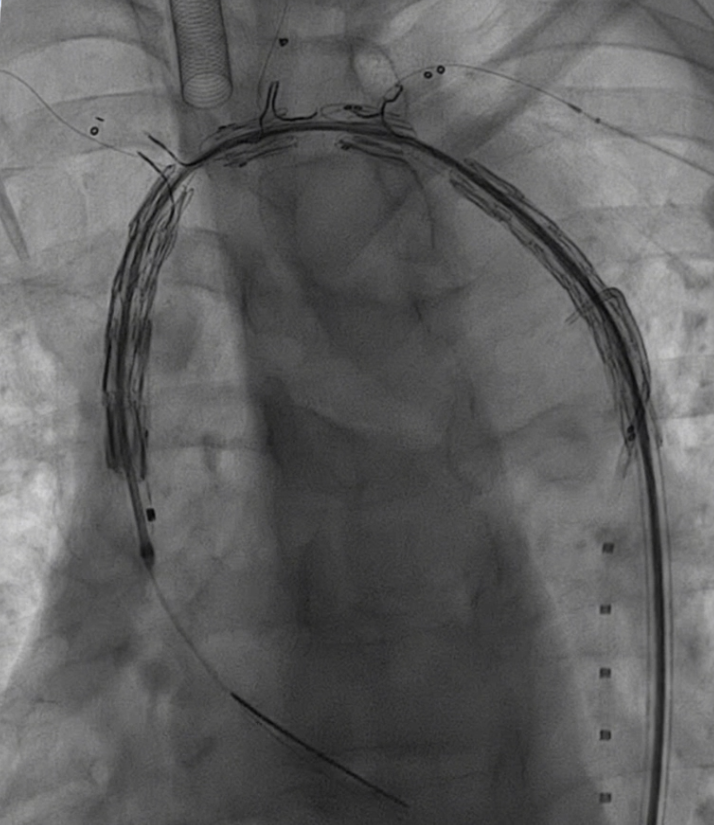

5. 支架释放与球囊预扩

释放支架主体,之后,头端后释放打开后将支架输送系统缓慢撤出。

分别经分支导丝送入球囊扩张支架分支覆膜部分,确保贴附良好。

6. 裸支架置入,球囊后扩张

于无名动脉、左颈总动脉及左锁骨下动脉开口位置处释放裸支架,维持血流通畅。

球囊后扩,优化支架形态及贴壁性,减少内漏风险。

手术效果及术后情况

术后造影显示,主动脉支架定位精准,三分支支架内血流通畅,夹层内仅有少量膜渗情况。从手术即刻效果来看,该治疗方案达到了预期目标,有效修复了主动脉夹层,恢复了血管的正常解剖结构和血流动力学状态。